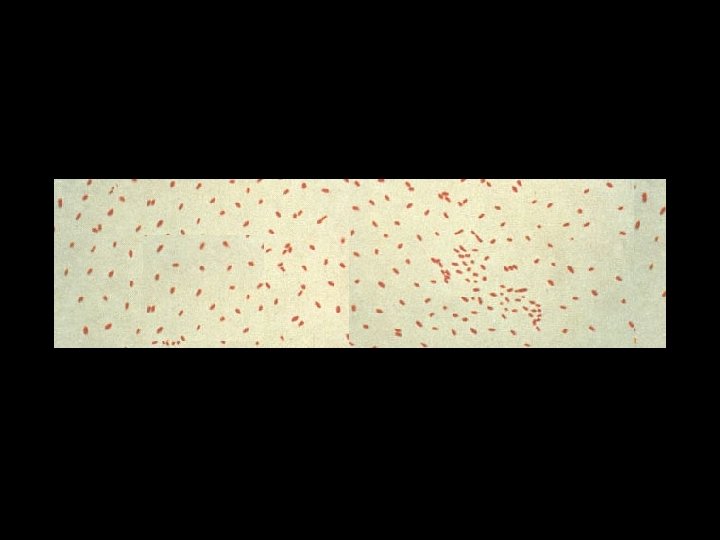

What kind of bacteria do you see?

Which bacterium do you suspect is the cause of the sore throat?

Streptococci Streptococcus pyogenes